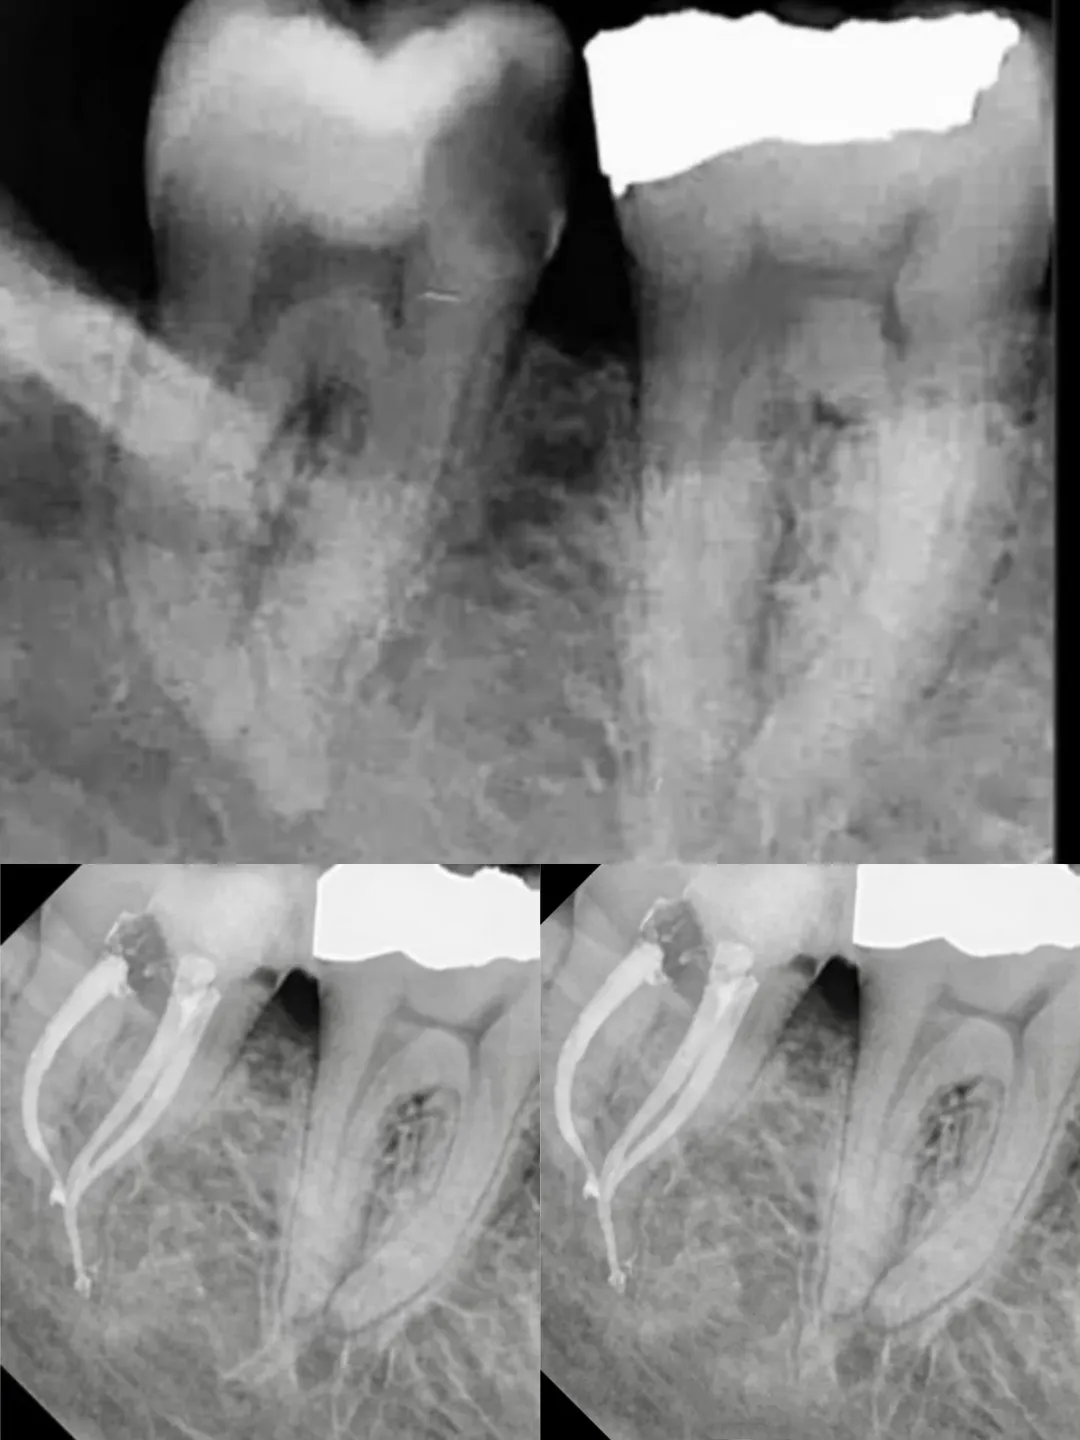

Dr. Mohammed Za'frany

Root Canal Files

AF - F ONE

Stainless Steel C Files

Treatment Case